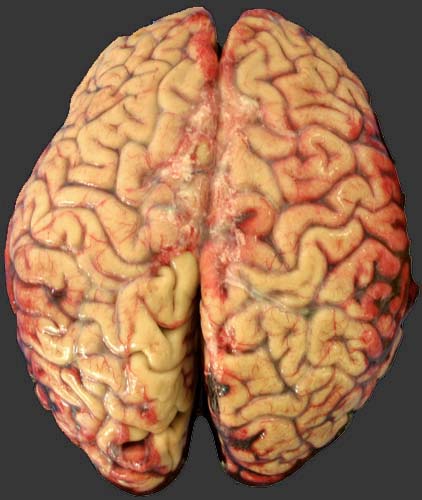

Внутреннее исследование: Туловище, шея, конечности абсолютно чистые, без единого повреждения! Черепно-мозговая травма (см. фото). От линейного максимум на 0,3 см вдавленного перелома на границе чешуи левой височной кости (в задней трети, идёт сверху-вниз, сзади-наперёд), который соответствовал ране на коже, отходят трещины и на основание черепа, где видны пероломы левой, правой основной кости и турецкого седла. Твёрдая мозговая оболочка без разрывов. Субдурально крови практически нет. Субарахноидально минимальные кровоизлияния (см. фото) в области удара и противоудара. Признаков сдавления, отёка гол. мозга нет. Ушибов не видно. Единственно, что обращает на себя внимание это смесь крови с ликвором в боковых желудочках, но не очень много.

Умер вроде бы от черепно-мозговой травмы. Ничего другого-то нет! Правда сильный запах алкоголя, но это вроде так себе.. попутно.

Вот представьте себе, что стою теперь рядом с трупом и тереблю бороду. Вскрытие закончено, а от чего хоронить? Ну понятно, что ЧМТ напишу, но самому не понятно отчего же он умер?

Как вы думаете достаточно ли этих повреждений чтобы его от ЧМТ "похоронить"? И от каких конкретно повреждений он вероянее всего умер?

Последнее фото с поверхностью распила/разреза. Никаких ушибов не видно!